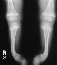

X-RAY STUDIES:

- "cupping" of the distal radius and distal femur

- widening of the physis

- angular deformities

10 months later on follow-up she had a noticeable decrease in her tibial

bowing along with almost complete resolution of the growth plate abnormalities.

At her last follow-up on March 4th 1996 (she was 4 + 4yo) she had mild

anterior lateral bowing of her tibia bilaterally with a normal thigh-foot

angle and a mechanical axis that crossed the midline of her knee.